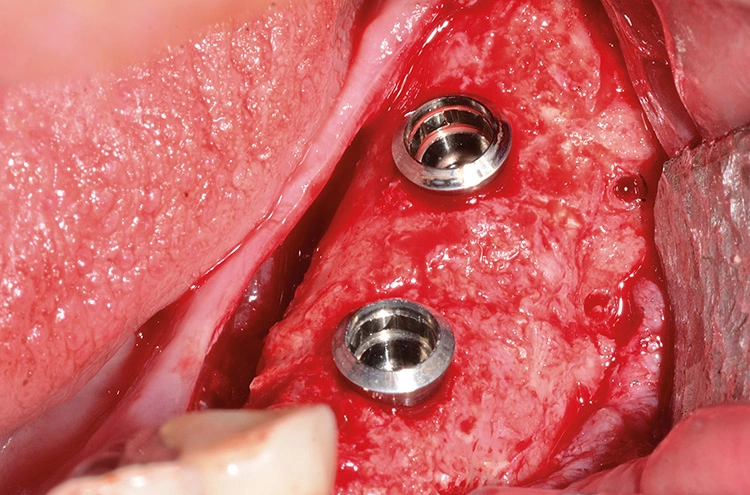

Implantation: 7 Monate nach Augmentation

Trotz der schlechten, hart- und weichgewebigen Grundvoraussetzungen konnte der Kieferkamm zufriedenstellend rekonstruiert werden. Die Augmentation des kombinierten, horizontalen und vertikalen Defekts mit Yxoss CBR®, Geistlich Bio-Oss®, Geistlich Bio-Gide®, autologem Knochen und PRF ermöglichte die Implantation mit hoher Primärstabilität in den rekonstruierten Bereich.